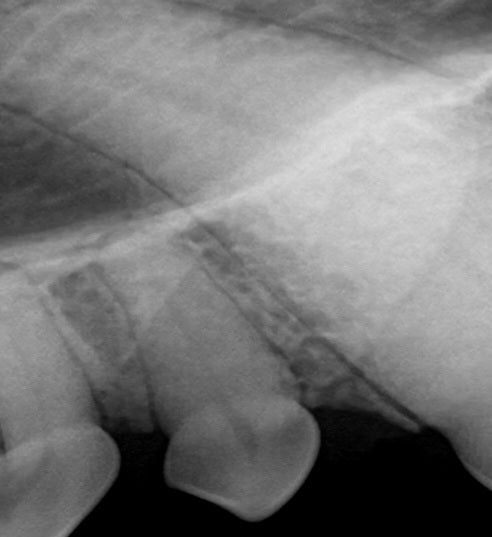

Olde Towne Animal Hospital is equipped with the latest in dental care including dental radiology, periodontal treatments, and even extractions when necessary. These technologies are important to help detect problems that are not immediately obvious but may become more extensive if not treated early.